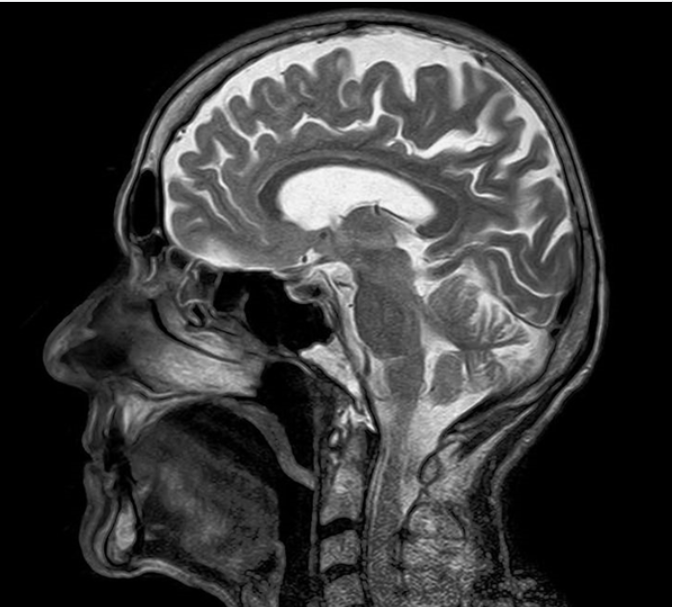

На снимках МРТ отчётливо визуализируются все основные структуры головного мозга: полушария, мозжечок, ствол мозга, желудочковая система и оболочки. Метод позволяет оценить состояние серого и белого вещества, выявить изменения в тканях, определить их локализацию и распространённость.

Также хорошо видны кровеносные сосуды (особенно при использовании специальных режимов или контрастирования), что позволяет оценить кровоснабжение мозга и выявить сосудистые патологии.